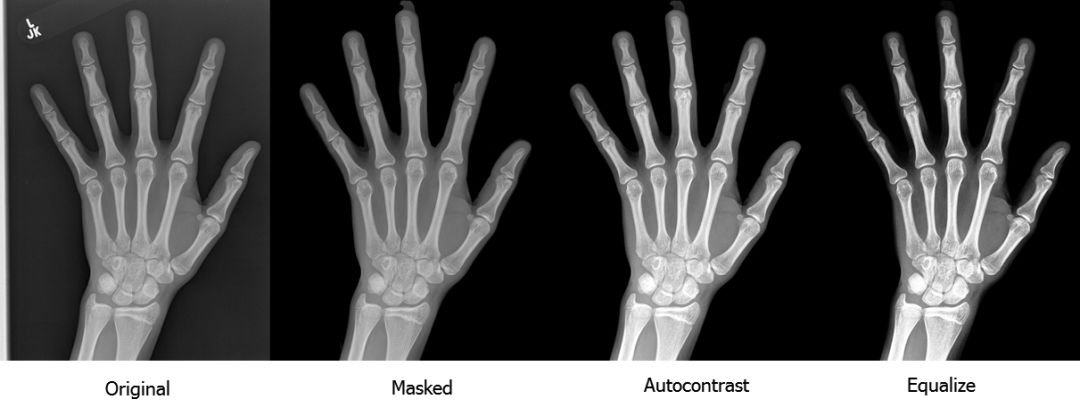

我们通过移除小的无关的连接组件和均衡对比度完成了分割步骤。下图是我们进行预处理的流程:

如你所见,放射图像的质量和对比度有了显著的提升。你可以到这里停止预处理,用我们的预处理方法和标准技术(如缩放和旋转)来增强训练集,然后训练一个标准的卷积神经网络用于分类或回归。我们试了这种方法,尽管结果不如我们的最终模型,但是也很令人满意。